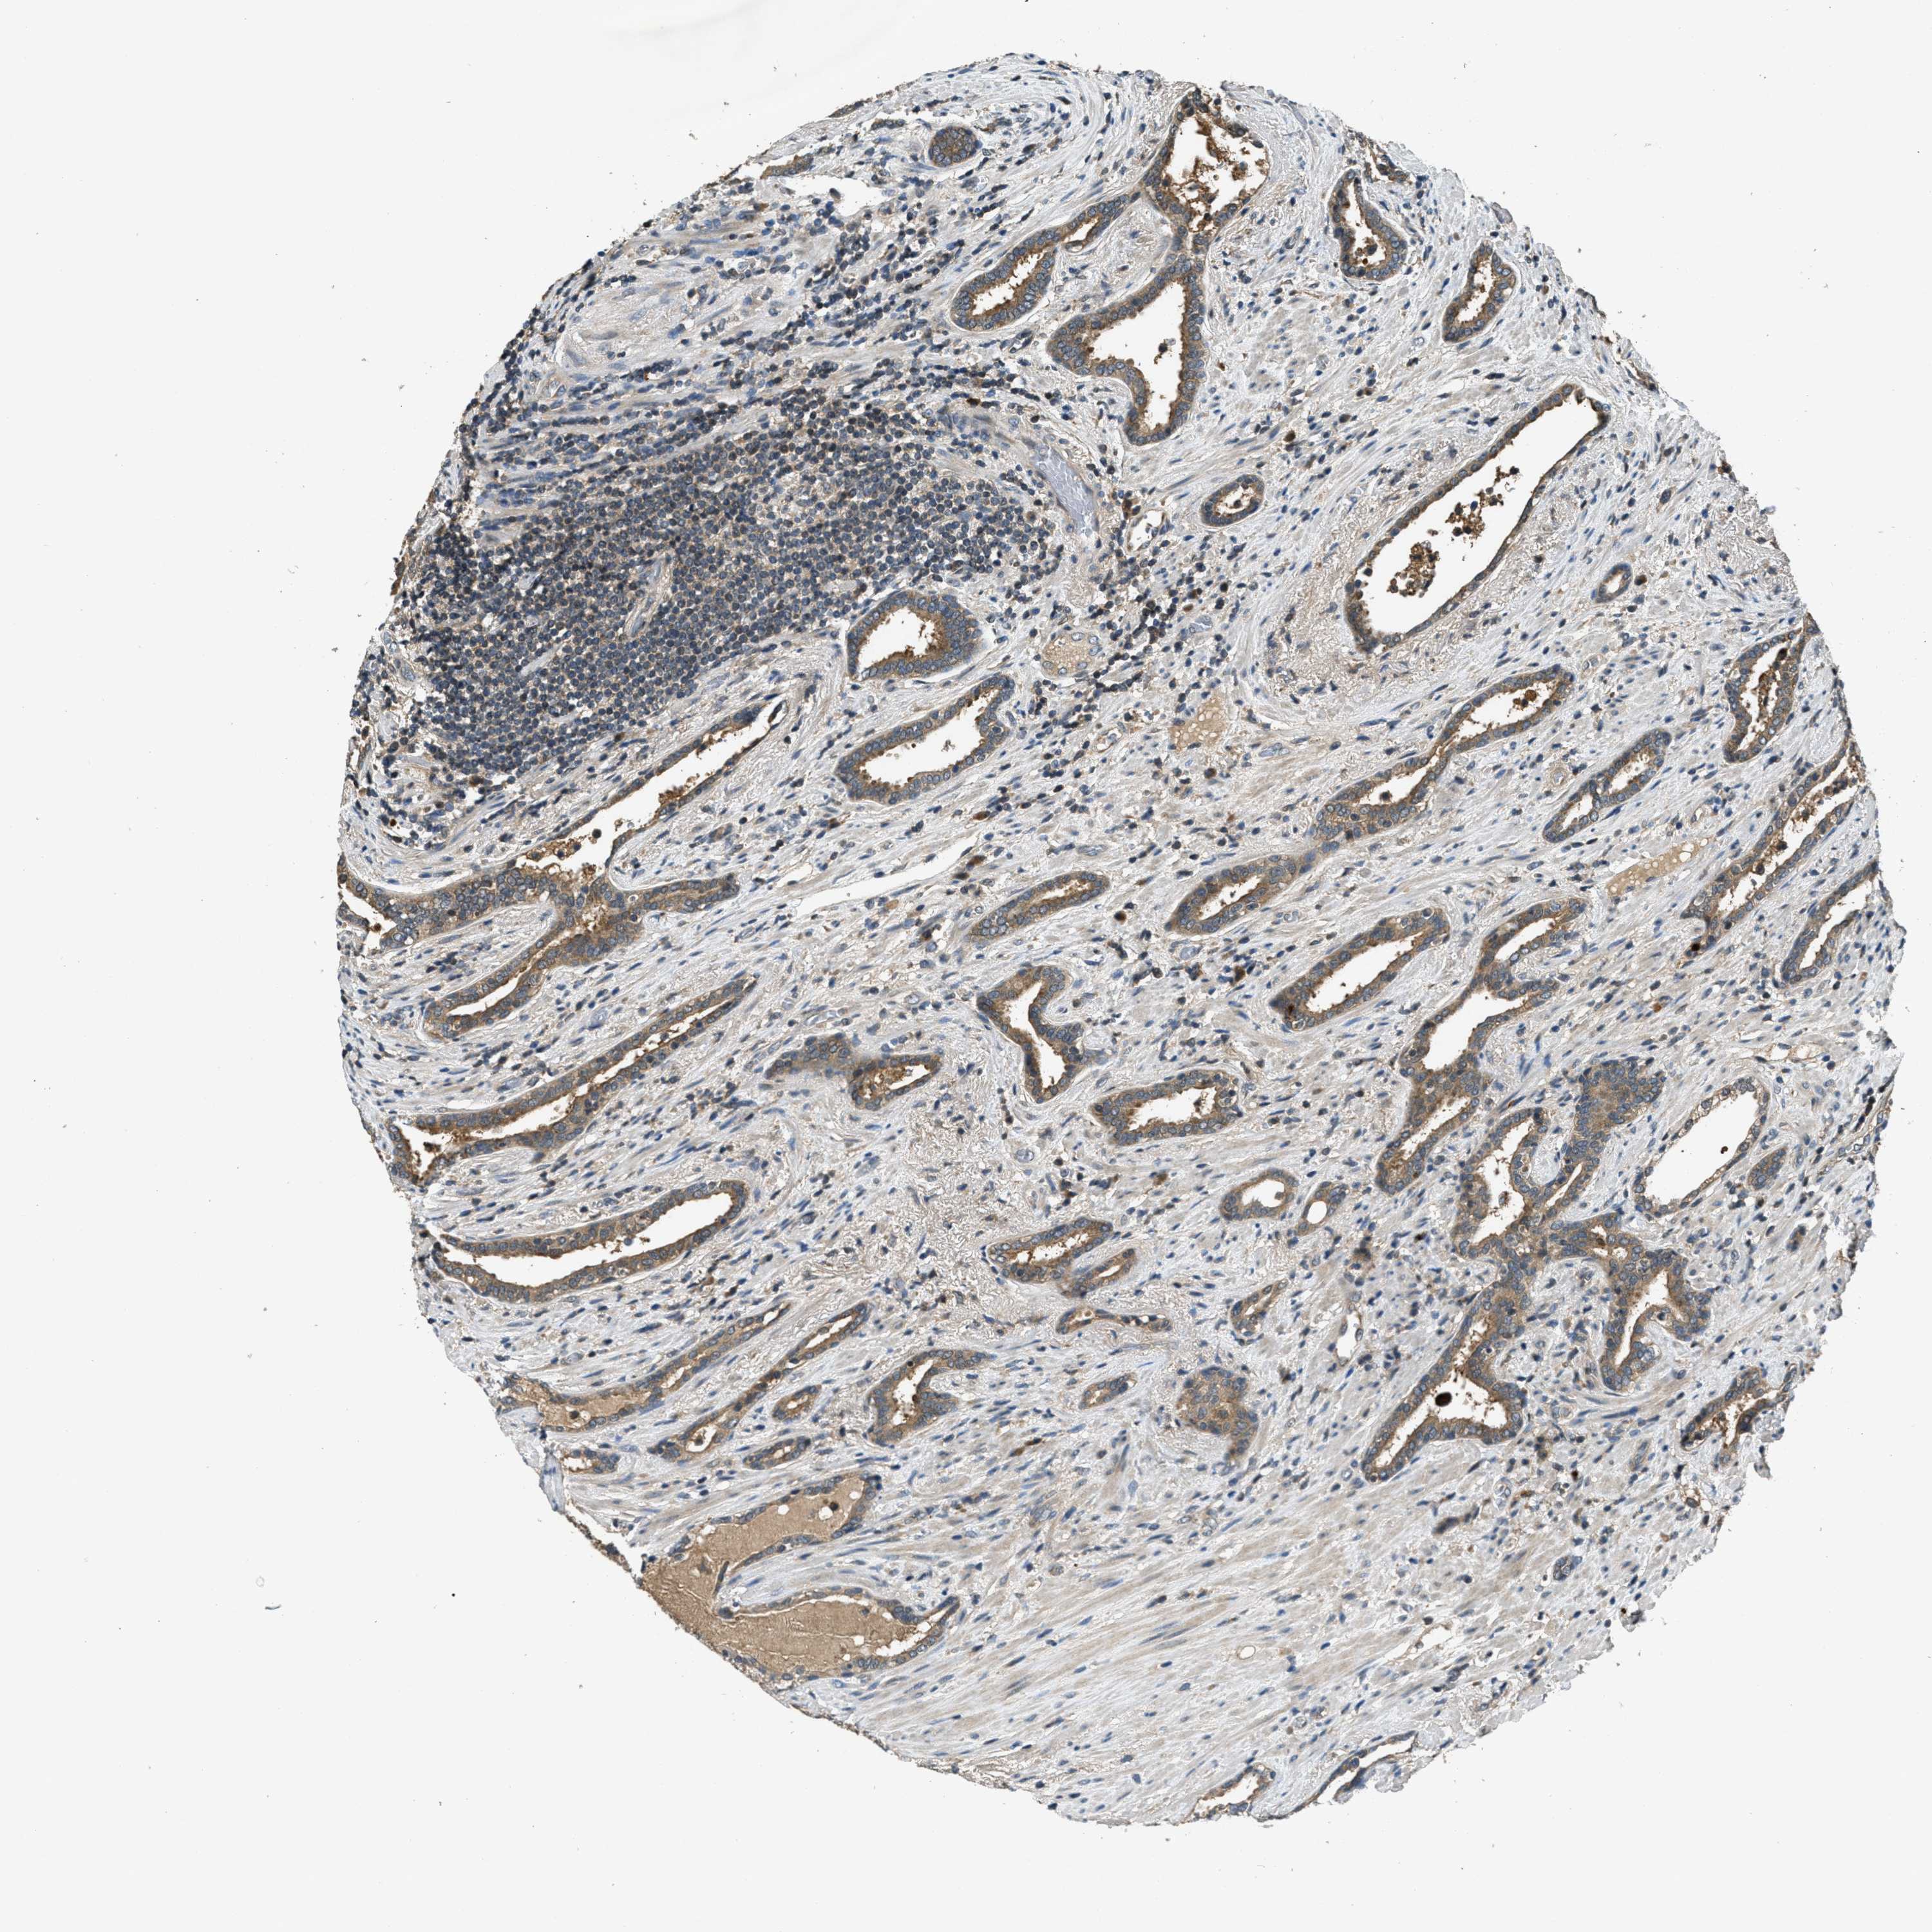

PROSTATE CANCER - Protein expressioni

A mouse-over function shows sample information and annotation data. Click on an image to view it in a full screen mode. Samples can be filtered based on level of antibody staining by selecting one or several of the following categories: high, medium, low and not detected. The assay and annotation is described here.

Note that samples used for immunohistochemistry by the Human Protein Atlas do not correspond to samples in the TCGA dataset.

Antibody stainingi

Antibody staining in the annotated cell types in the current human tissue is reported as not detected, low, medium, or high, based on conventional immunohistochemistry profiling in selected tissues. This score is based on the combination of the staining intensity and fraction of stained cells.

Each image is clickable and will lead to virtual microscopy that enables deeper exploration of all samples and also displays staining intensity scores, fraction scores and subcellular localization as well as patient and tissue information for each sample.

Antibody CAB017566

Staining

High

Medium

Low

Not detected

Intensity

Strong

Moderate

Weak

Negative

Quantity

>75%

75%-25%

<25%

None

Location

Nuclear

Cytoplasmic/membranous

Cytoplasmic/membranous,nuclear

Adenocarcinoma, High grade

Adenocarcinoma, Low grade